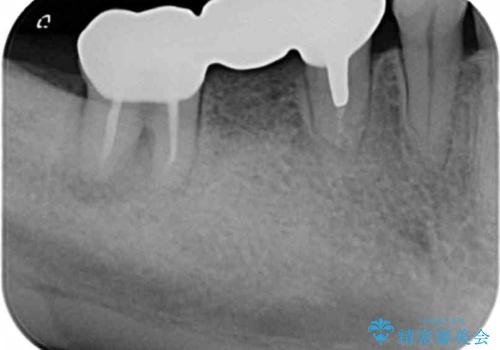

ブリッジを支える歯が割れてしまい、抜歯が必要であることと、骨の大きな吸収が見られました。

インプラント治療を行うにあたり周囲に骨を造成することで安定して噛める環境の整備を計画します。

今回はインプラント埋入時に固定が得られたので同時に骨の造成を行い治療を進めることができました。